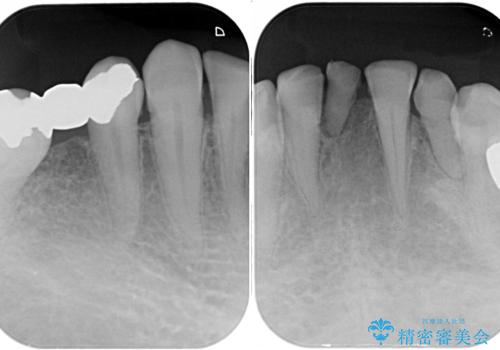

下顎の乳歯は支台歯として機能することは困難と思われたので、事前に抜歯をし、上顎の矯正治療終了のタイミングに合わせて、セラミックブリッジにて補綴治療することとしました。

前歯部はディープバイトという、上顎前歯が下顎前歯に深く覆い被さる咬合であったので、理想的には全顎矯正が必要となりますが、今回は患者希望により前歯部のみの部分矯正で対応しました。そのため下顎犬歯の神経を取り除くことになってしまったのは心残りであります。